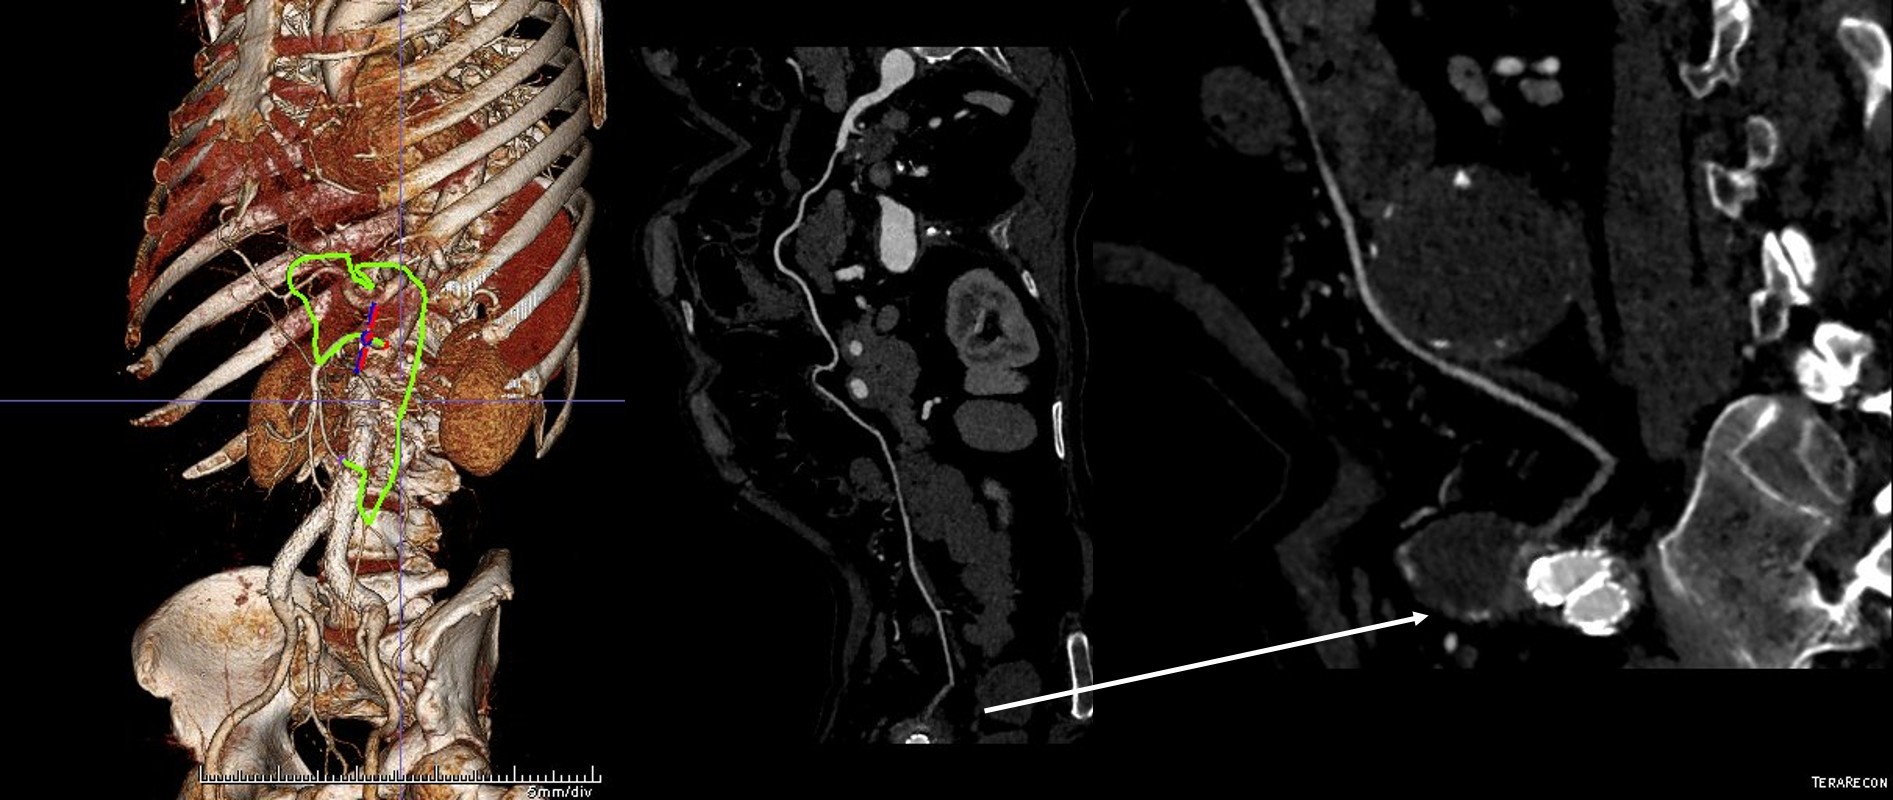

The patient had a successful EVAR or an eccentric infrarenal AAA which in followup grew due to the presence of a type II endoleak from the inferior mesenteric artery. This was seen on the CTA and duplex ultrasound. Planning for assessment and treatment involved analyzing the CTA in centerline, tracking the source of the arterial blood flow into the sac.

The centerline from the SMA into the middle colic artery shows a meandering but patent path via the Arc of Riolan to the left colic artery to the inferior mesenteric artery. In my experience this is straightforward to access selectively from the femoral approach, but it illustrates for the trainees the concept of building up access which I refer to as building the intervention machine.

The CTA is particularly helpful in identifying the middle colic on the 3DVR projection. Selection of this is straightforward with a an angle catheter which I place a Tuohy Borst connector. This is the second stage of the machine, because further access with 0.35guage wires and catheters could result in spasm. This second sheath access (the Tuohy turns the catheter into a sheath) of the middle colic allows for selective 0.18 gauge catheters and wires to make the final step to the IMA and the AAA.